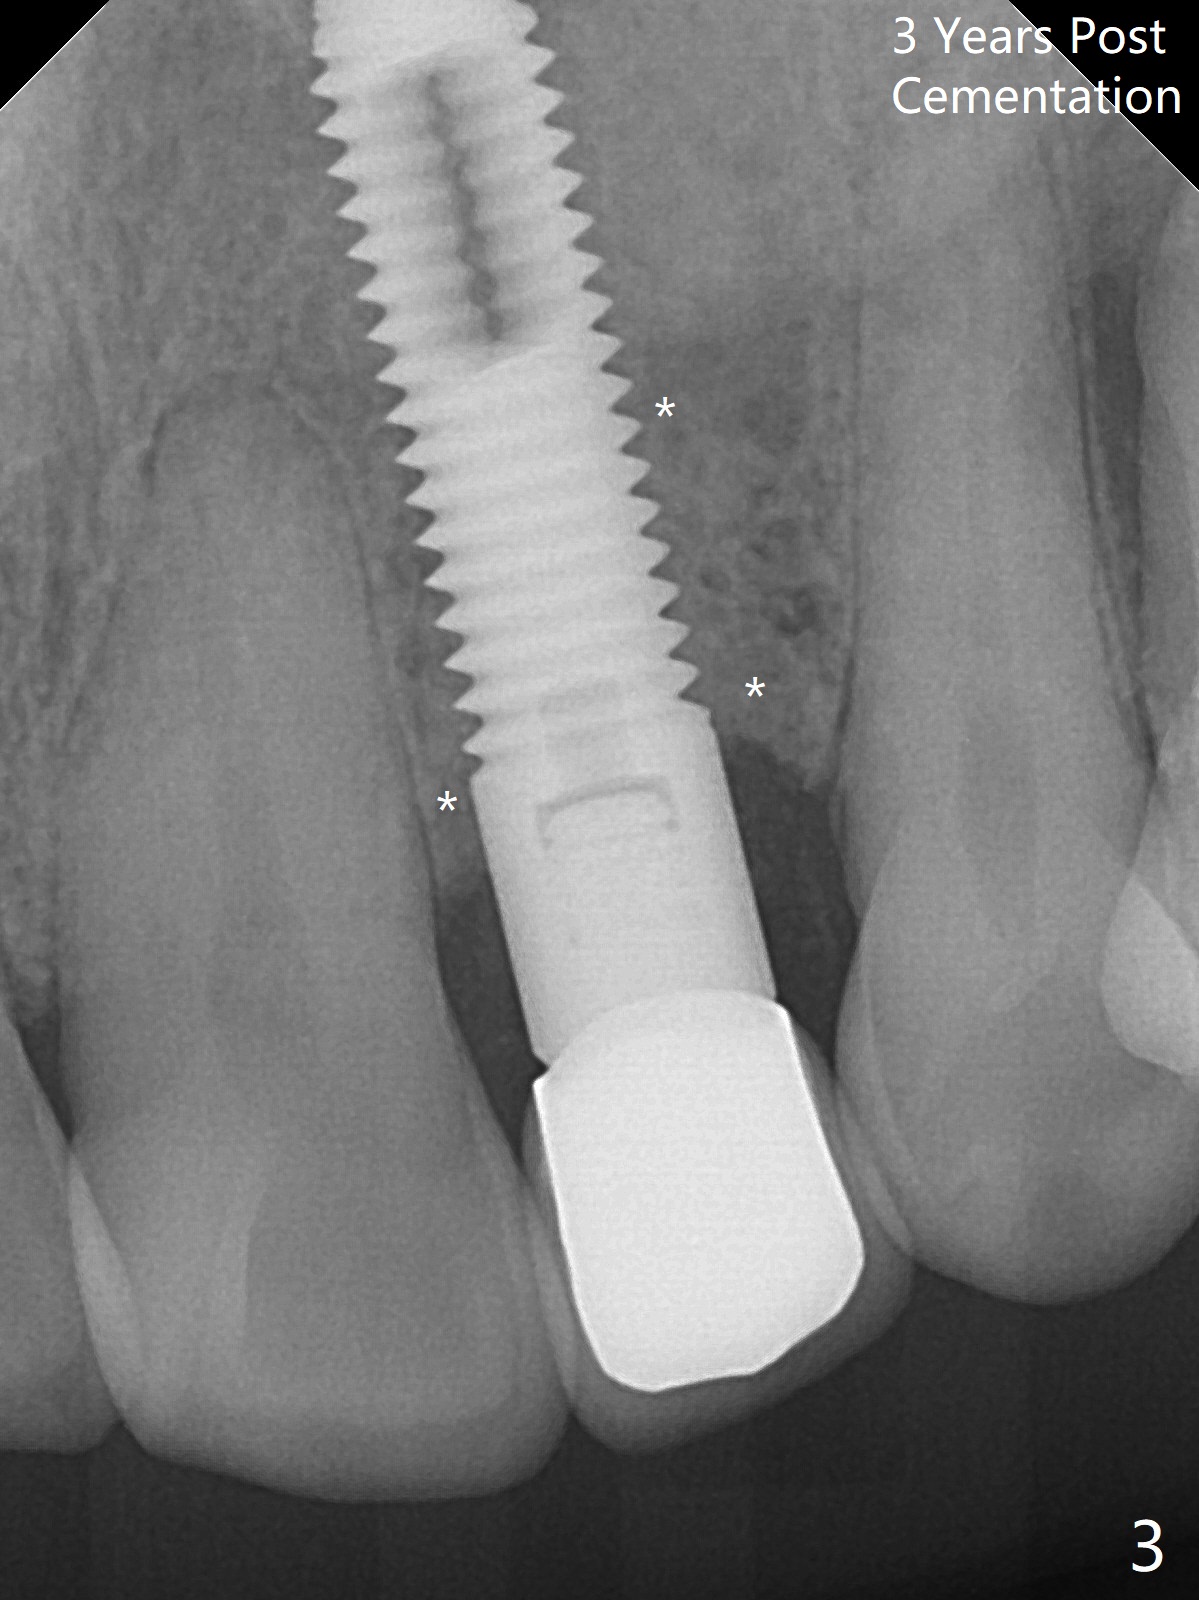

A 61-year-old man has chronic periodontitis and bruxism (Fig.1). Immediately after extraction and Clindamycin socket treatment, osteotomy is initiated with a 2 mm pilot drill at 20 mm in the lower 1/3 of palatal wall with normal saline irrigation, followed by 2.5-4 mm reamers at 20 mm (bone saved, Type III bone). A screw Implant (4.5x20 mm) is placed (45-50 Ncm, Fig.2). The root measurements were B-L 6.5 mm and M-D 5 mm. Autogenous bone is mixed SynthoGraft (size 50-500) ~ .3 g and blood. A 3.5x5 mm abutment is immediately cemented with an immediate provisional. There is positive bone growth 3 years post cementation (Fig.3 *). There is no buccal plate bone resorption 3 years 2 months post cementation (Fig.4 CT).